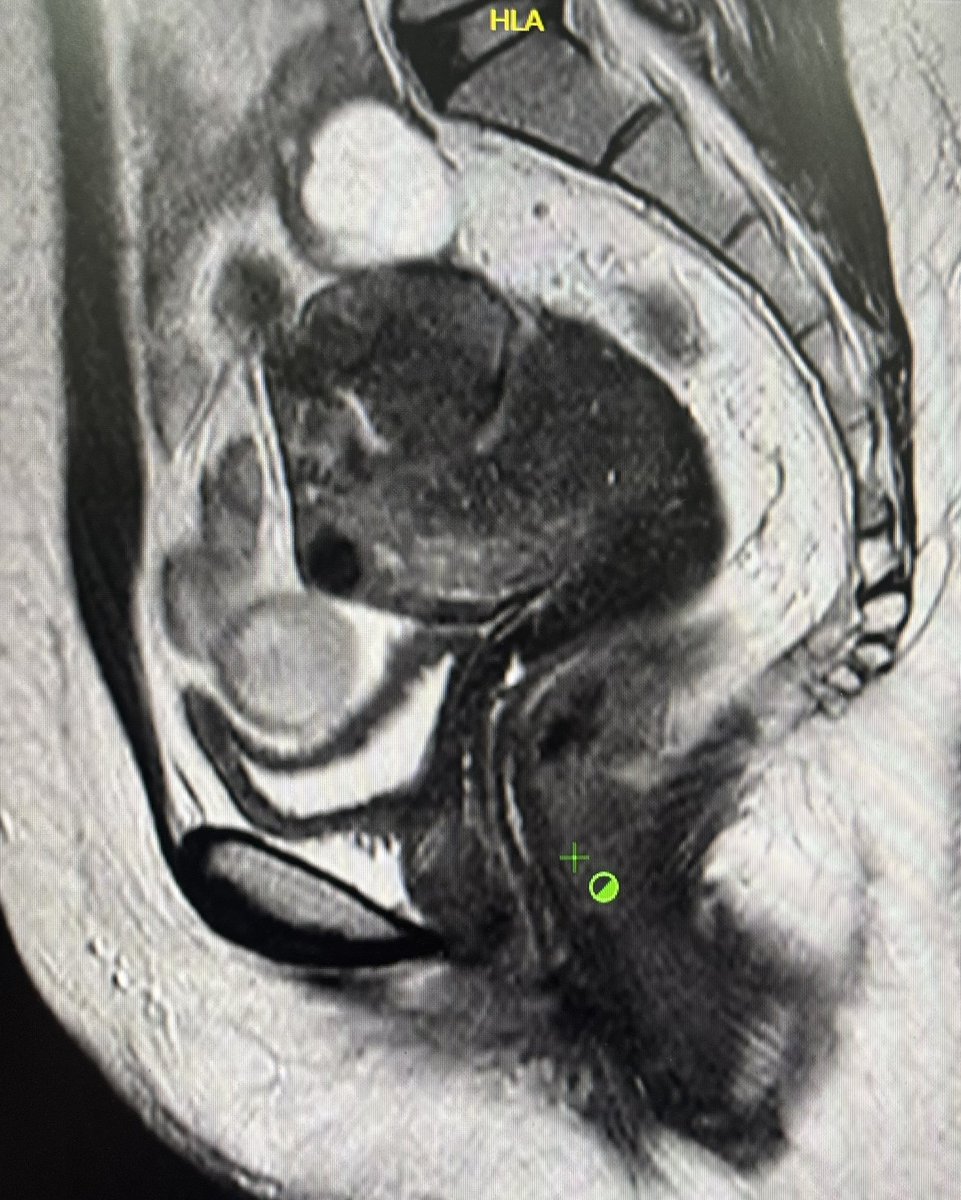

@DrYevSam_Rad Focal Adenomyosis of the Outer Myometrium (FAOM)/External Adenomyosis -

low T2-signal intensity region within the outer myometrium, most often posteriorly.

Look for ill-defined margins, minimal mass effect, and possible punctate hyperintense foci

FAOM can coexist with DIE

This lady might have silently suffered for over a decade now and turned up for MRI Pelvis for as a part of infertility work up.

Hoping to diagnose more such cases on USG earlier so they don’t end up like this 🤞